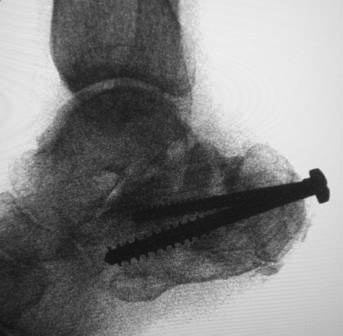

Уважаемый коллега, в случае Вашего пациента положительным моментом является отсутствие деформации пятки в горизонтальной (аксиальный) плоскости, что несколько упрощает остеотомию в планируемой операции. Но надо отметить, что имеется выраженная посттравматическая деформация в сагитальной плоскости со значительным сдвигом места крепления ахиллова сухожилия к переди, что снижает эффективность действия мышц задней группы голени. Моё предложение - клиновидная (с основанием вниз) корригирующая остеотомия бугра пяточной кости, закрытая ахиллотомия. Но, поскольку деформация значительная, стремиться полностью восстановить анатомические ориентиры не стоит. Фиксацию предлогаю Осуществить 2 винтами типа Барука (7,0).

Уважаемые коллеги. Операция была произведена 22.01.16г., только сегодня имеется возможность отправить. L-образный доступ. . при ревизии подтаранный сустав сохранен, поэтому линейная остеотомия, подкожная ахиллотомия. Подготовка ложа, и смещенный отломок спущен вниз к ложу , но до конца не смогли. Фиксирован двумя винтами. По медиальной поверхности рубец плотно спаянный с костным осколком, пока не трогали из-за опасения инфицирования, после заживления раны потом будем думать, что делать.

Аксиальная Р-грамма вышло некачественно, потому что гипс наложен в положении некоторого эквинуса.